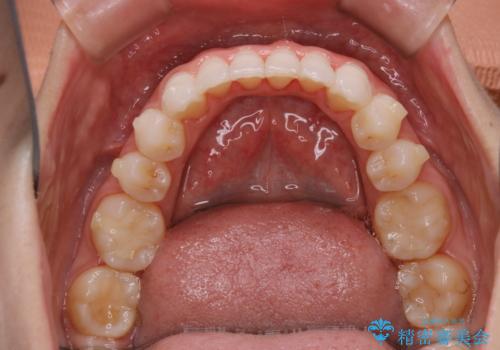

インビザラインで矯正治療中に、クリーニングを行ったbeforeafter写真です。